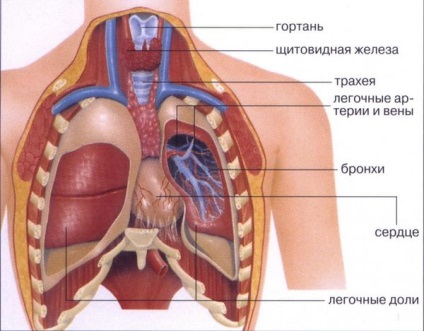

Az emberi mellkas szerkezetét az oszteokondrális szöveti álló 12 csigolya, azonos számú bordák, szegycsont.

Vegyület alkatrészeket ízületek és szalagok. Belül egy mellüreg, elhelyezésére a legfontosabb emberi szervek:

- tüdő

A legnagyobb szerv a szervezetben üreget megtöltjük a nagyobb térfogatú. Megkülönböztetni a jobb és bal tüdőt. Bal különböző részvények száma (kettő), és a görbület a bal oldalon. Funkció - amely a test oxigénnel. - légcső

Foglal el köztes álláspontot hörgők és a gége, áll a porc és a kötőszövet alsó ágai két hörgőket áramlik a jobb és a bal tüdőben. Funkció - amely a kínálat, a levegő a tüdőbe, légtisztító infekciókontroll. - nyelőcső

Összeköti a torok és a gyomor, áthaladva a mellüregben, izom gyűrűk lehetővé teszik a bolus mozgatni a gyomorban. Funkció - biztosítani az emésztést. - szív

Található között a tüdő, nyúlványa van elhelyezve felfelé a jobb hátsó, a nyak - a lejtőn lefelé a bal oldalon, van egy bonyolult szerkezet és az izmok az üregek útján, amely test mozgásának támogatott, a mérete eltérő. A legszélesebb része az arc a nagy hajókat. Külsőleg, a test és a hajók borítja védő ruha - szívburok. Feature - a vér átáramlik a hajók, hogy fenntartsa a véráramlást.

Elhelyezkedés szervek a mellkasban